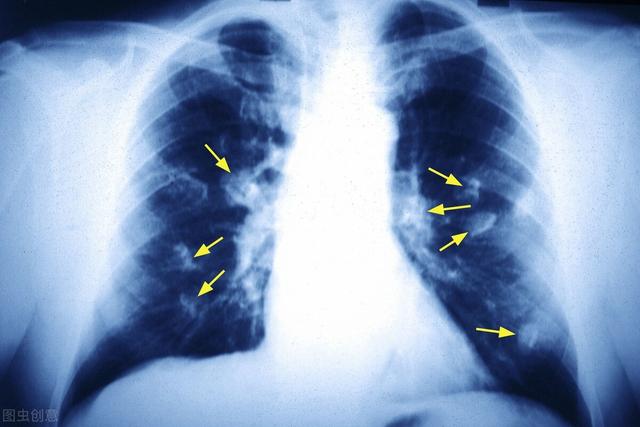

最近这几年,肺癌是所有癌症中发病率最高的,特别是在工业大城市中,严重威胁人们的生命健康。肺癌早期并没有症状,80%患者就诊时已经达到晚期。随着医学发达,多种方法能治疗肺癌,如手术、放疗化疗和靶向治疗等。目前为止,根治性切除是唯一可能会让肺癌患者获得治愈,恢复正常生活的治疗手段。不过手术后若想让肺功能恢复正常,需重点保护呼吸道。